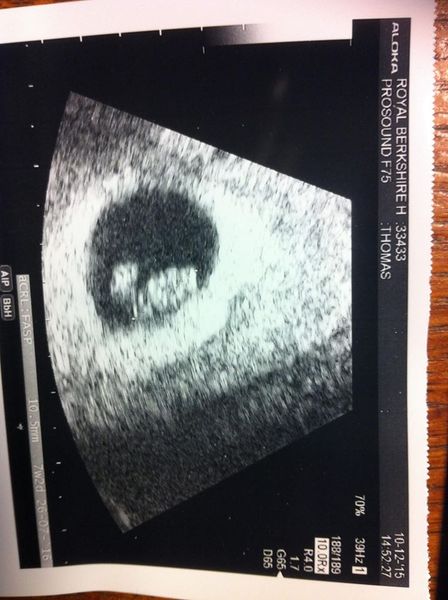

However I had my clinic appointment yesterday and the scan went well, looked like a little shrimp and heart beat was healthy, I am 7+3 today and am due 26th July.

Here's my little shrimp!

HI Mord - lovely to hear from you. I'm so glad all is ok, you must be so relieved. It's so brilliant to see your scan pic, little shrimp with heart beating away. great news! I'm sure you'll get blood sugar under control, I'd say trying to keep calm is great start.

Thanks all for your kind words. Roll on the 23rd! Mord - that is a lovely scan picture!

lovely pic mord a lovely little shrimp Smile so sorry you've had such a stressful time of it, that sounds horrible. So glad everything seems to be working out ok.